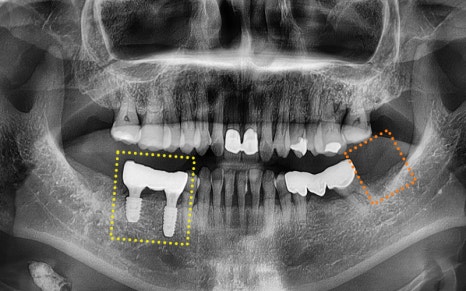

She was experiencing pain in the lower molars on both sides,

and we took a panoramic X-ray

to check the situation in detail.

🦷 Summary of the condition at the time of the visit

✔ The first lower molar on the right

had already been extracted

✔ The second lower molar on the right

was judged to be difficult to preserve due to tooth fracture,

so extraction was decided

✔ The second premolar had a crown already in place,

and it was part of a bridge connected

to the second lower molar

✔ The lower left wisdom tooth

needed extraction due to inflammation